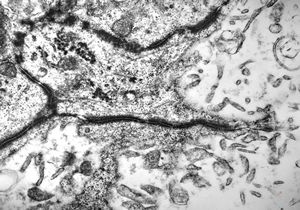

F,50y. | progressive multifocal leukoencephalopathy- viral particles in a glial cell